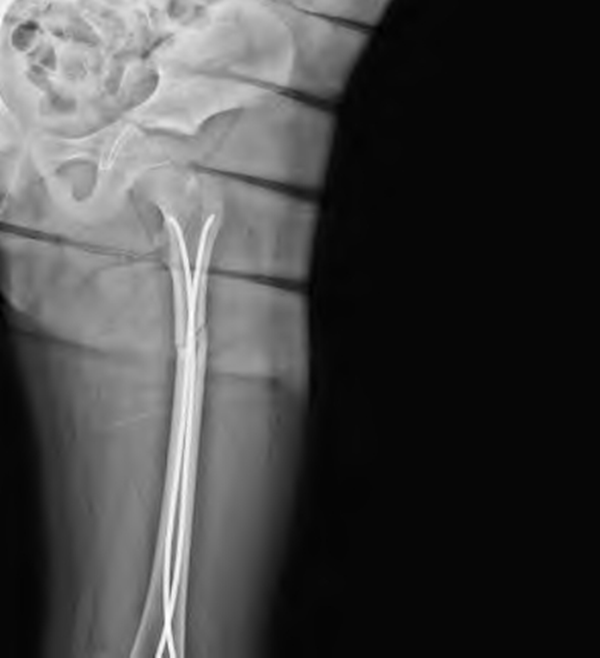

1.弹性髓内钉内固定:目前对于儿童股骨干骨折的治疗,弹性髓内钉是最常见的的内固定方式。弹性髓内钉是利用3点支撑的原理,通过手术的方式将进钉点、髓内钉弧弓顶点、髓内钉钉头与股骨髓腔内内壁形成一个稳定的支撑结构。具体操作为在股骨远端骺板上方内外侧各插入1枚相同直径弹性髓内钉,直径约为髓腔最窄处直径约1/3,钉尾露在皮质外0.5~1.0cm,于髓内成“X”形的6点固定。其优点在于弹性髓内钉操作过程中不需要扩髓,骨折断端不需要切开,不需要剥离骨膜,对骨折端血供影响小,固定后骨折断端的纵向微动,不产生应力遮挡,符合生物力学特性。目前,对于3岁以上儿童股骨干骨折,选用弹性髓内钉内固定进行治疗,均获得了满意疗效。弹性髓内钉内固定治疗也存在局限性,其抗旋转能力较差,对于长斜形或长螺旋形等不稳定性股骨干骨折,常会出现骨折断端再次移位、弹性钉退钉、股骨长度丢失等并发症。但是也有学者对儿童不稳定性股骨干骨折应用弹性髓内钉并配合螺钉内固定、尾帽技术、加用第3根弹性钉方法,以增加稳定性,获得满意疗效。弹性髓内钉出现的并发症主要为针尾激惹、抗旋转能力差、畸形愈合、股骨长短丢失等。临床上随着使用的增多,其缺点及并发症逐渐出现,建议对一些年龄较大或体重大于50Kg患儿限制弹性髓内钉使用。

弹性髓内钉治疗儿童股骨干骨折